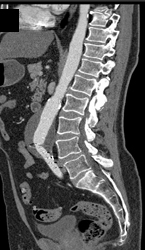

Diagnosis

Stent in Aortic W/o Endoleak